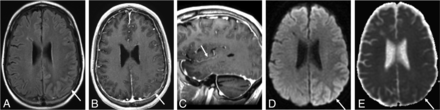

A 51-year-old man with a history of juvenile left posterior fossa tumor treated by surgery and whole-brain irradiation 45 years ago presented with acute visual changes and seizures. He was diagnosed with SMART syndrome and treated with corticosteroids and recovered from the symptoms. A FLAIR image (A) shows cortical hyperintensity, and the postcontrast T1 image (B) shows gyriform enhancement in the right temporo-occipital region (arrows), with an incidental right temporal dural-based meningioma. There is high signal on diffusion-weighted imaging (C) without low signal on ADC (D) (facilitated diffusion) (arrows).

Imaging plays a crucial role of the diagnosis of SMART syndrome, and brain MR imaging is the primary imaging technique of choice.2⇓-4 In the acute phase of SMART syndrome, the typical MR imaging features are seen as reversible, unilateral, gyriform enhancement with T2 and FLAIR hyperintense cortical swelling in a distribution not consistent with vascular territories (Fig 2).2⇓⇓-5 Findings are typically unilateral, likely reflecting the distribution of the high-dose radiation treatment field, though there are a few reports of bilateral cerebral involvement.22 Involvement of the temporal and parietal lobes is often reported, followed by the occipital and frontal lobes.4,8,22 In the delayed phase, the conventional MR imaging features as well as symptoms resolve or become mitigated. Previous reports showed that gyriform enhancement typically resolves in 14–35 days but may last up to 84 days.4 There have been many reports regarding additional imaging features of conventional neuroimaging, advanced neuroimaging, and nuclear medicine imaging. In this section, we discuss additional imaging features of SMART syndrome that are not currently included in the diagnostic criteria but are important for assessment and prognosis. We also review imaging features of variants of SMART syndrome including PIPG and ALERT.